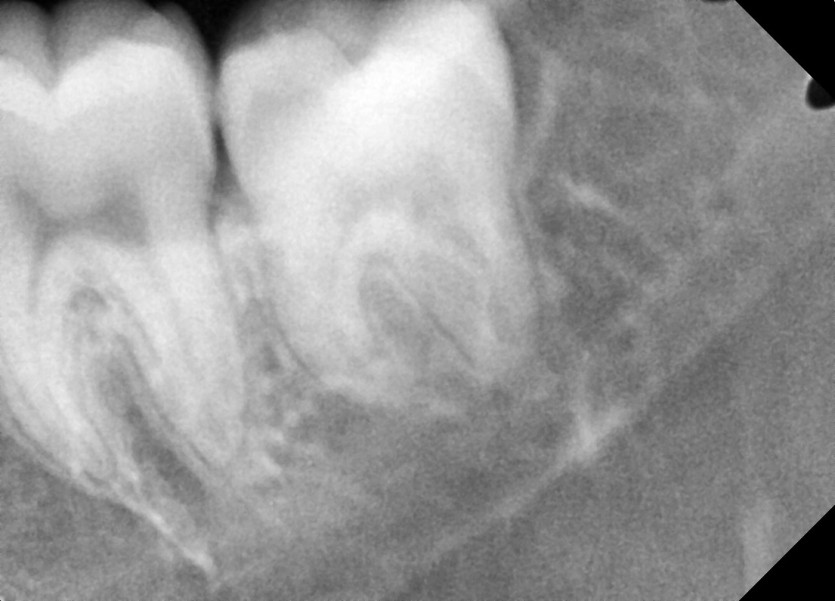

#28,38 사랑니 발치

구강 외과 전문의가 당일 발치했습니다.